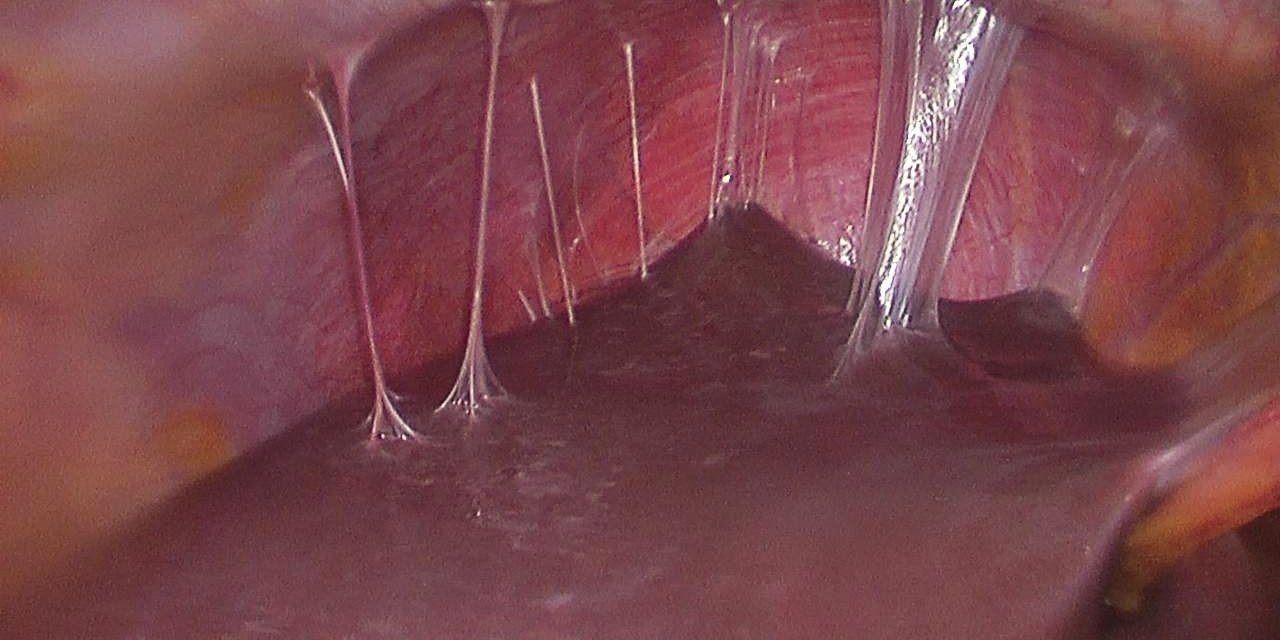

Dr. Ovayolu: “Kanama sorunu olan hasta izsiz cerrahi ile 12 saatte sağlığına kavuştu”